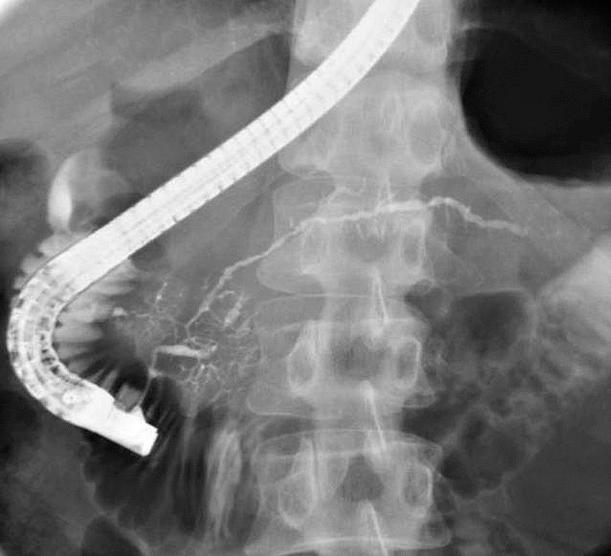

76歳の男性。黄疸を主訴に来院した。3日前に家族に皮膚の黄染を指摘されていた。3年前に唾液腺腫瘤を摘出した。飲酒は機会飲酒。意識は清明。身長168cm、体重57kg。体温36.4℃。呼吸数16/分。脈拍72/分、整。血圧126/82mmHg、眼球結膜に黄染を認める。心音と呼吸音とに異常を認めない。肝・牌を触知しない。尿所見:蛋白(-)、糖1+。血液所見:赤血球465万、Hb14.1g/dL、Ht45%、白血球8,100、血小板16万。血液生化学所見:血糖201mg/dL、HbA1c 6.7%(基準4.3〜5,8)、総蛋白9.6g/dL、アルブミン4.6g/dL、尿素室素19mg/dL、クレアチニン0.5mg/dL、総ピリルビン6.8mg/dL、AST86lU/L、ALT78IU/L、LD540IU/L(基準176〜353)、ALP1,230IU/L(基準115〜359)、Na138mEq/L、K4.OmEq/L、Cl102mEq/L。免疫学所見:CRP O.8mg/dL、抗核抗体 陽性、IgG 3,890mg/dL(基準739〜1,649)、IgA 118mg/dL(基準107〜363)、IgM 132mg/dL(基準46〜260)、CEA 2.8ng/mL(基準5以下)、CA19-9 26U/mL(基準37以下)。腹部造影CTと内視鏡的逆行性胆管膵管造影写真

検査では、軽度の肝機能障害、抗核抗体陽性、IgG高値あたり、画像では、膵臓がやたらでかい(CT)、胆管の先細り(ERCP)、膵管の狭小化・壁不正あたりが特徴らしい。私はこの疾患をよく知らないので適当なことを言ってるかもしれない。